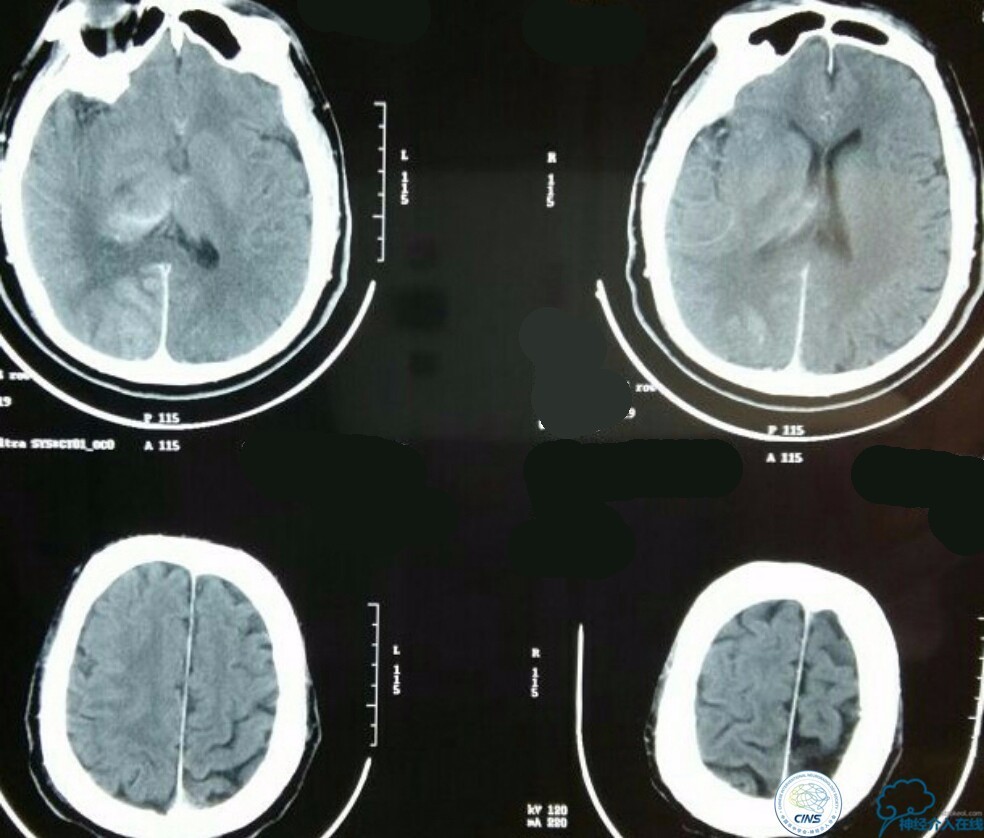

急诊MRI+MRA:右侧丘脑及小脑半球多发新鲜梗死病灶,右侧颈内动脉颅内段未见显影,基底动脉尖未见显影!

造影结果:右侧颈总动脉远端闭塞,前交通动脉开放,代偿方式:左侧颈内动脉→左侧大脑前动脉A1→前交通动脉→右侧大脑前动脉A1(反向)→右侧大脑中动脉供血区代偿。双侧大脑后动脉、右侧小脑上动脉及基底动脉顶端未见显影。

结合病史,体征及影像学,考虑患者本次发病为基底动脉尖急性闭塞,发病机制:栓塞?右侧颈总动脉慢性闭塞?非责任血管,且代偿良好,暂时不需处理!